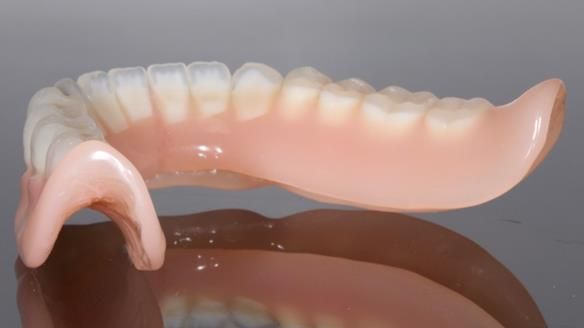

In this edition, I present the complete denture treatment for Kate, a 69-year-old American woman living in Garstang, UK. Kate had been edentulous for many years and required a set of complete dentures that closely mimicked her natural teeth. The new upper and lower dentures provided excellent retention and stability, with significant suction in the upper denture. Below, I detail the step-by-step process of her treatment, as well as my workflow for implant-supported overdentures for patients who may require them.

The treatment was a resounding success, meeting all of Kate’s expectations. While I was confident I could achieve a natural appearance, the challenges of gagging, denture stability, and eating were less predictable and uncertain. I discussed these concerns thoroughly at the outset, and Kate decided to proceed despite the high cost. She expressed that there was no pressure to move forward with the treatment, and she’s been delighted with the life-changing results.

Treatment Process: I provided the clinical work while Rowan Garstang and Sam Hesketh delivered the technical aspects. The treatment required fifteen visits to fit and review Edgar.